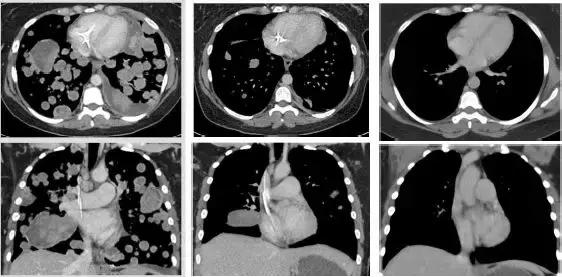

其中有一些晚期患者的病灶完全消失了:

我们可以清楚的看到,这位极晚期的肉瘤患者,肿瘤已经快要填满双肺,经过LOXO-101治疗12周期,肿瘤几乎完全消失!

治疗前 治疗3周期第1天 治疗13周期第1天